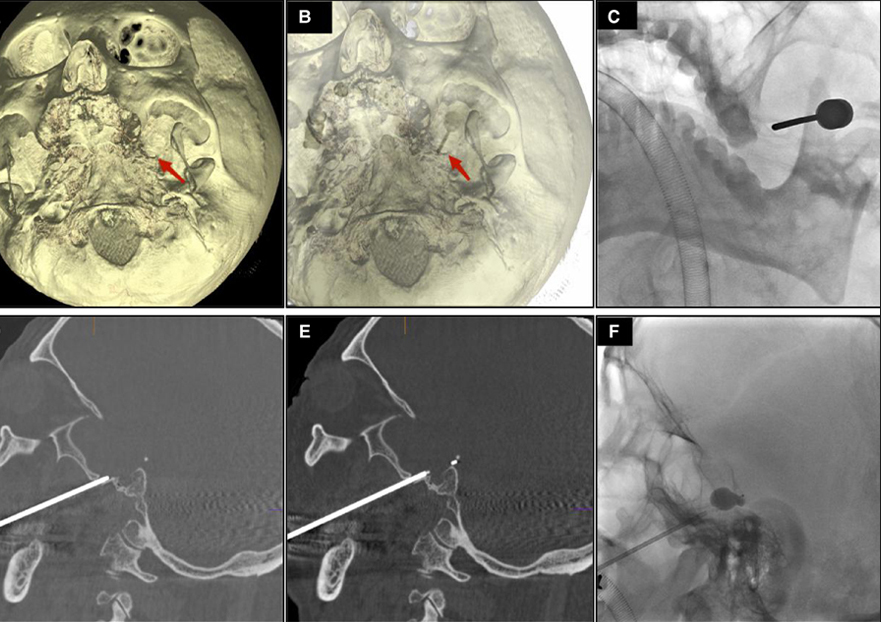

Department of Neurosurgery of Zhuhai People’s Hospital has successfully conducted 24 Percutaneous Balloon Compression operations using SYM Medical’s PBC sets during the period of October 2020 and September 2021.All surgeries were successful. The research has shown that preoperative multimodal image reconstruction can help fully evaluate PBC surgery, clarify the etiology, and predict the volume of contrast medium required during the operation.